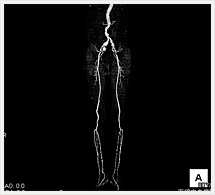

CTでは輪切り像の他にも立体的な画像(3D画像)を作成することもできます。そのためにはより細かくキレイな画像を撮影しなければなりません。当院では64列CTを導入しており、キレイな画像をより細かく撮影することができます。その画像を元に3D画像を作成することによって、より正確な手術のシミュレーションが可能になります。実際に手術をしたときの様子が、手術をする前に画像として見らます。外科系の手術には欠かせない技術となっておりますが、内科系でも血管内手術にも多く利用されております。

当診療放射線技術科では毎日各診療科に対して、その手術に最適な3D画像を提供しております。

以下にその3D画像を一部分紹介します。

下肢動脈